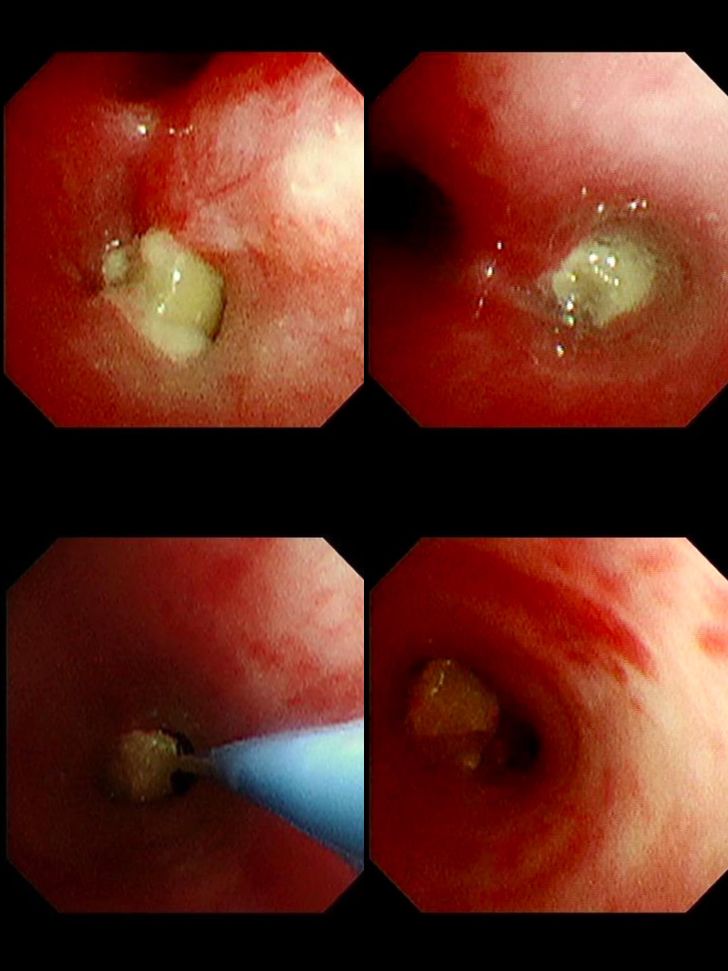

ทีมแพทย์นำโดยสามีของคุณหมอเลี่ยว ต้องรีบทำการส่องกล้องหลอดลมเพื่อคีบเอาถั่วลิสงออกมา แต่ทว่าไม่ง่ายอย่างที่คิด เพราะถั่วเม็ดนั้นติดค้างมานานหลายวันจนมีเนื้อเยื่ออักเสบงอกขึ้นมาหุ้ม (Granulation Tissue) ทำให้ถั่วติดแน่นในหลอดลมที่เล็กจิ๋ว ทีมงานต้องใช้ความพยายามอย่างหนักเกือบ 2 ชั่วโมง กว่าจะจับเจ้า "ถั่วเต้นระบำ" ที่ลื่นไหลไปมาออกมาได้สำเร็จ

แต่ในความเป็นจริง สิ่งที่หมอเห็นในห้องฉุกเฉินคือ ภาพของหลอดลมที่อักเสบบวมเป่ง เนื้อเยื่อที่เน่าเปื่อย ปอดที่แฟบลง และเด็กตัวเล็กๆ ที่ต้องนอนใส่ท่อช่วยหายใจใน ICU ซึ่งเป็นภาพที่น่าเวทนาและป้องกันได้ 100%